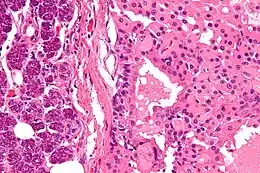

La tumeur est constituée de cellules oncocytaires éosinophiles. Les noyaux des oncocytomes sont toujours ronds et réguliers (par opposition aux noyaux des carcinomes à cellules chromophobes qui sont, au contraire, anguleux, rainurés et avec inclusion cytoplasmique).